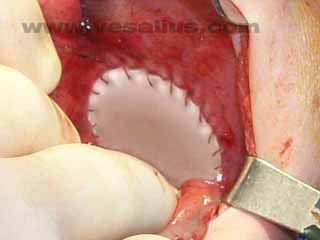

| When the defect is too large, a mesh may be required to cover the defect. |